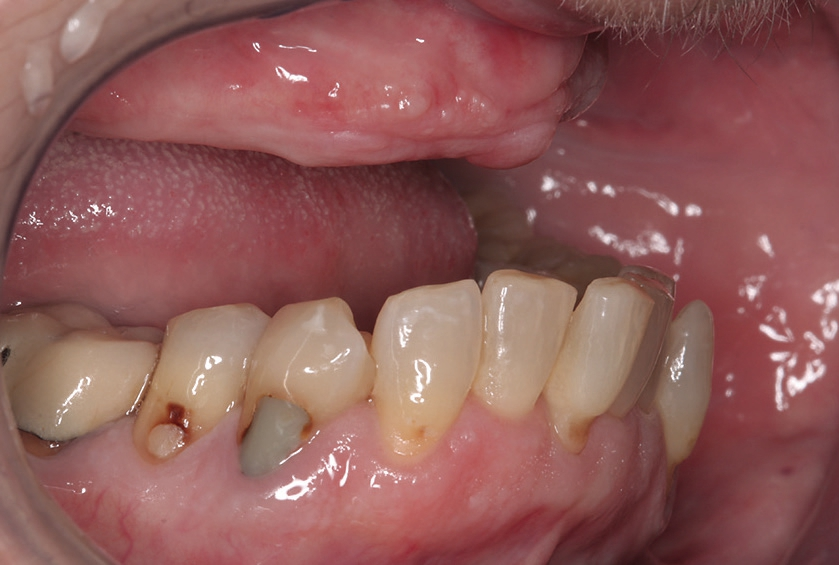

Der vorliegende Fall beschreibt die orale Rehabilitation einer 65 Jahre alten Patientin im Oberkiefer (Abb. 1 und 2). Der atrophierte Oberkiefer weist eine sagittale Stufe zum Unterkiefer auf. Dies macht eine komplett festsitzende Versorgung von vorneherein schwer umsetzbar. Die Patientin wünschte sich dennoch einen ästhetisch ansprechenden Zahnersatz und eine langzeitstabile Lösung. Die konservierende Behandlung des Unterkiefers wurde im Rahmen der ganzheitlichen Sanierung von uns ebenfalls geplant und durchgeführt.

Die präimplantologische Behandlung bestand in der Sanierung insuffizienter konservierender Versorgungen und einer Parodontalbehandlung, um mögliche Infektionsquellen am Restzahnbestand zu entfernen.